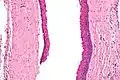

Odontogenic keratocysts have a diagnostic histological appearance. Under the microscope, OKCs vaguely resemble keratinized squamous epithelium;[14] however, they lack rete ridges and often have an artifactual separation from their basement membrane.[2]

The fibrous wall of the cyst is usually thin and uninflamed. The epithelial lining is thin with even thickness and parakeratinised with columnar cells in the basal layer which have focal reverse polarisation (nuclei are on the opposite pole of the cell).[12] The basal cells are an indication of the odontogenic origin as they resemble pre-ameloblasts. The epithelium can separate from the wall, resulting in islands of epithelium. These can go on to form 'satellite' or 'daughter' cysts, leading to an overall multilocular cyst.[9] Presence of daughter cysts is particularly seen in those with NBCCS.[12] Inflamed cysts show hyperplastic epithelium which is no longer characteristic of OKCs and can have resemblance to radicular cysts instead. Due to areas of focal inflammation, a larger biopsy is required for correct diagnosis of odontogenic keratocysts.[9]

High magnification of an odontogenic keratocyst.